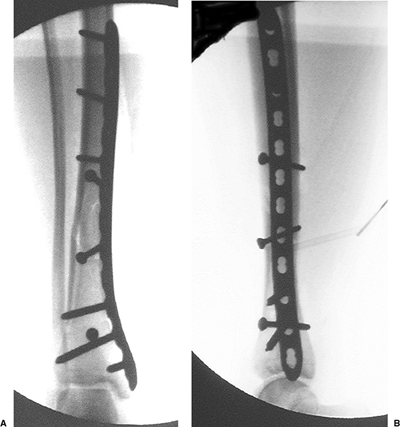

Figure 28.12. AP (A) and lateral (B)

intraoperative images after removal of the ATD. The proximal screws are standard, 4.5-mm, cortical screws and the distal screws are 5.0-mm locked screws. Due to fracture configuration, additional lag screws through or outside the plate were not necessary. |